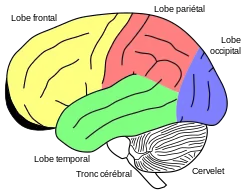

Des études neurologiques récentes ont permis une localisation plus précise des lésions cérébrales de Gage. La barre métallique a en partie détruit le cortex préfrontal, c'est-à-dire la partie du cortex cérébral située au plus près du front. Dans ce cas, ce n'est que la partie ventromédiale du cortex préfrontal qui a été endommagée (voir figure). Les études neuropsychologiques ont montré que Gage n'est pas un cas unique. Tous les patients qui ont une lésion dans le cortex préfrontal ventromédiale présentent cette perte des capacités émotionnelles, malgré une conservation des capacités intellectuelles.

Signification de la recherche neurologique

Toutefois, ce n'est pas exclusivement le cortex préfrontal ventromédiale qui est impliqué dans les décisions morales. Beaucoup d'auteurs font remarquer qu'il n'existe pas de « centre moral » dans le cerveau[35],[36]. Les décisions morales surviennent bien plus d'une interaction complexe entre émotions et pensées. Et même pour les émotions à caractère moral, on constate qu'elles concernent plusieurs régions du cerveau. Une région importante est l'amygdale qui n'est pas située dans le cortex cérébral, mais dans une région plus profonde (subcorticale). Des lésions dans cette région conduisent à la perte de capacités émotionnelles.